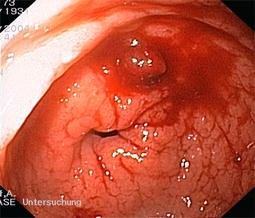

Abb. 4